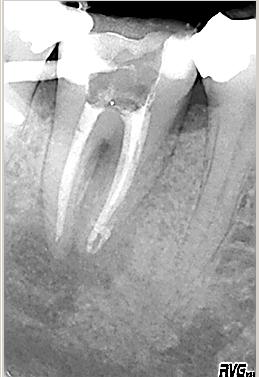

Röntgenmessaufnahme

Röntgenmessaufnahme im November 2002 nach vorgängig durchgeführter endometrischer Längenbestimmung. Zuerst erfolgte der adhäsive Aufbau des Zahnes mit anschließender Trepanation

Masterpointaufnahme

Erste Kontrolle direkt nach Wurzelfüllung mit vertikaler Kondensation erwärmter Guttapercha mit System B und Obtura 2. Man beachte die dreidimensionale Füllung der Seitenkanäle der mesialen Wurzel